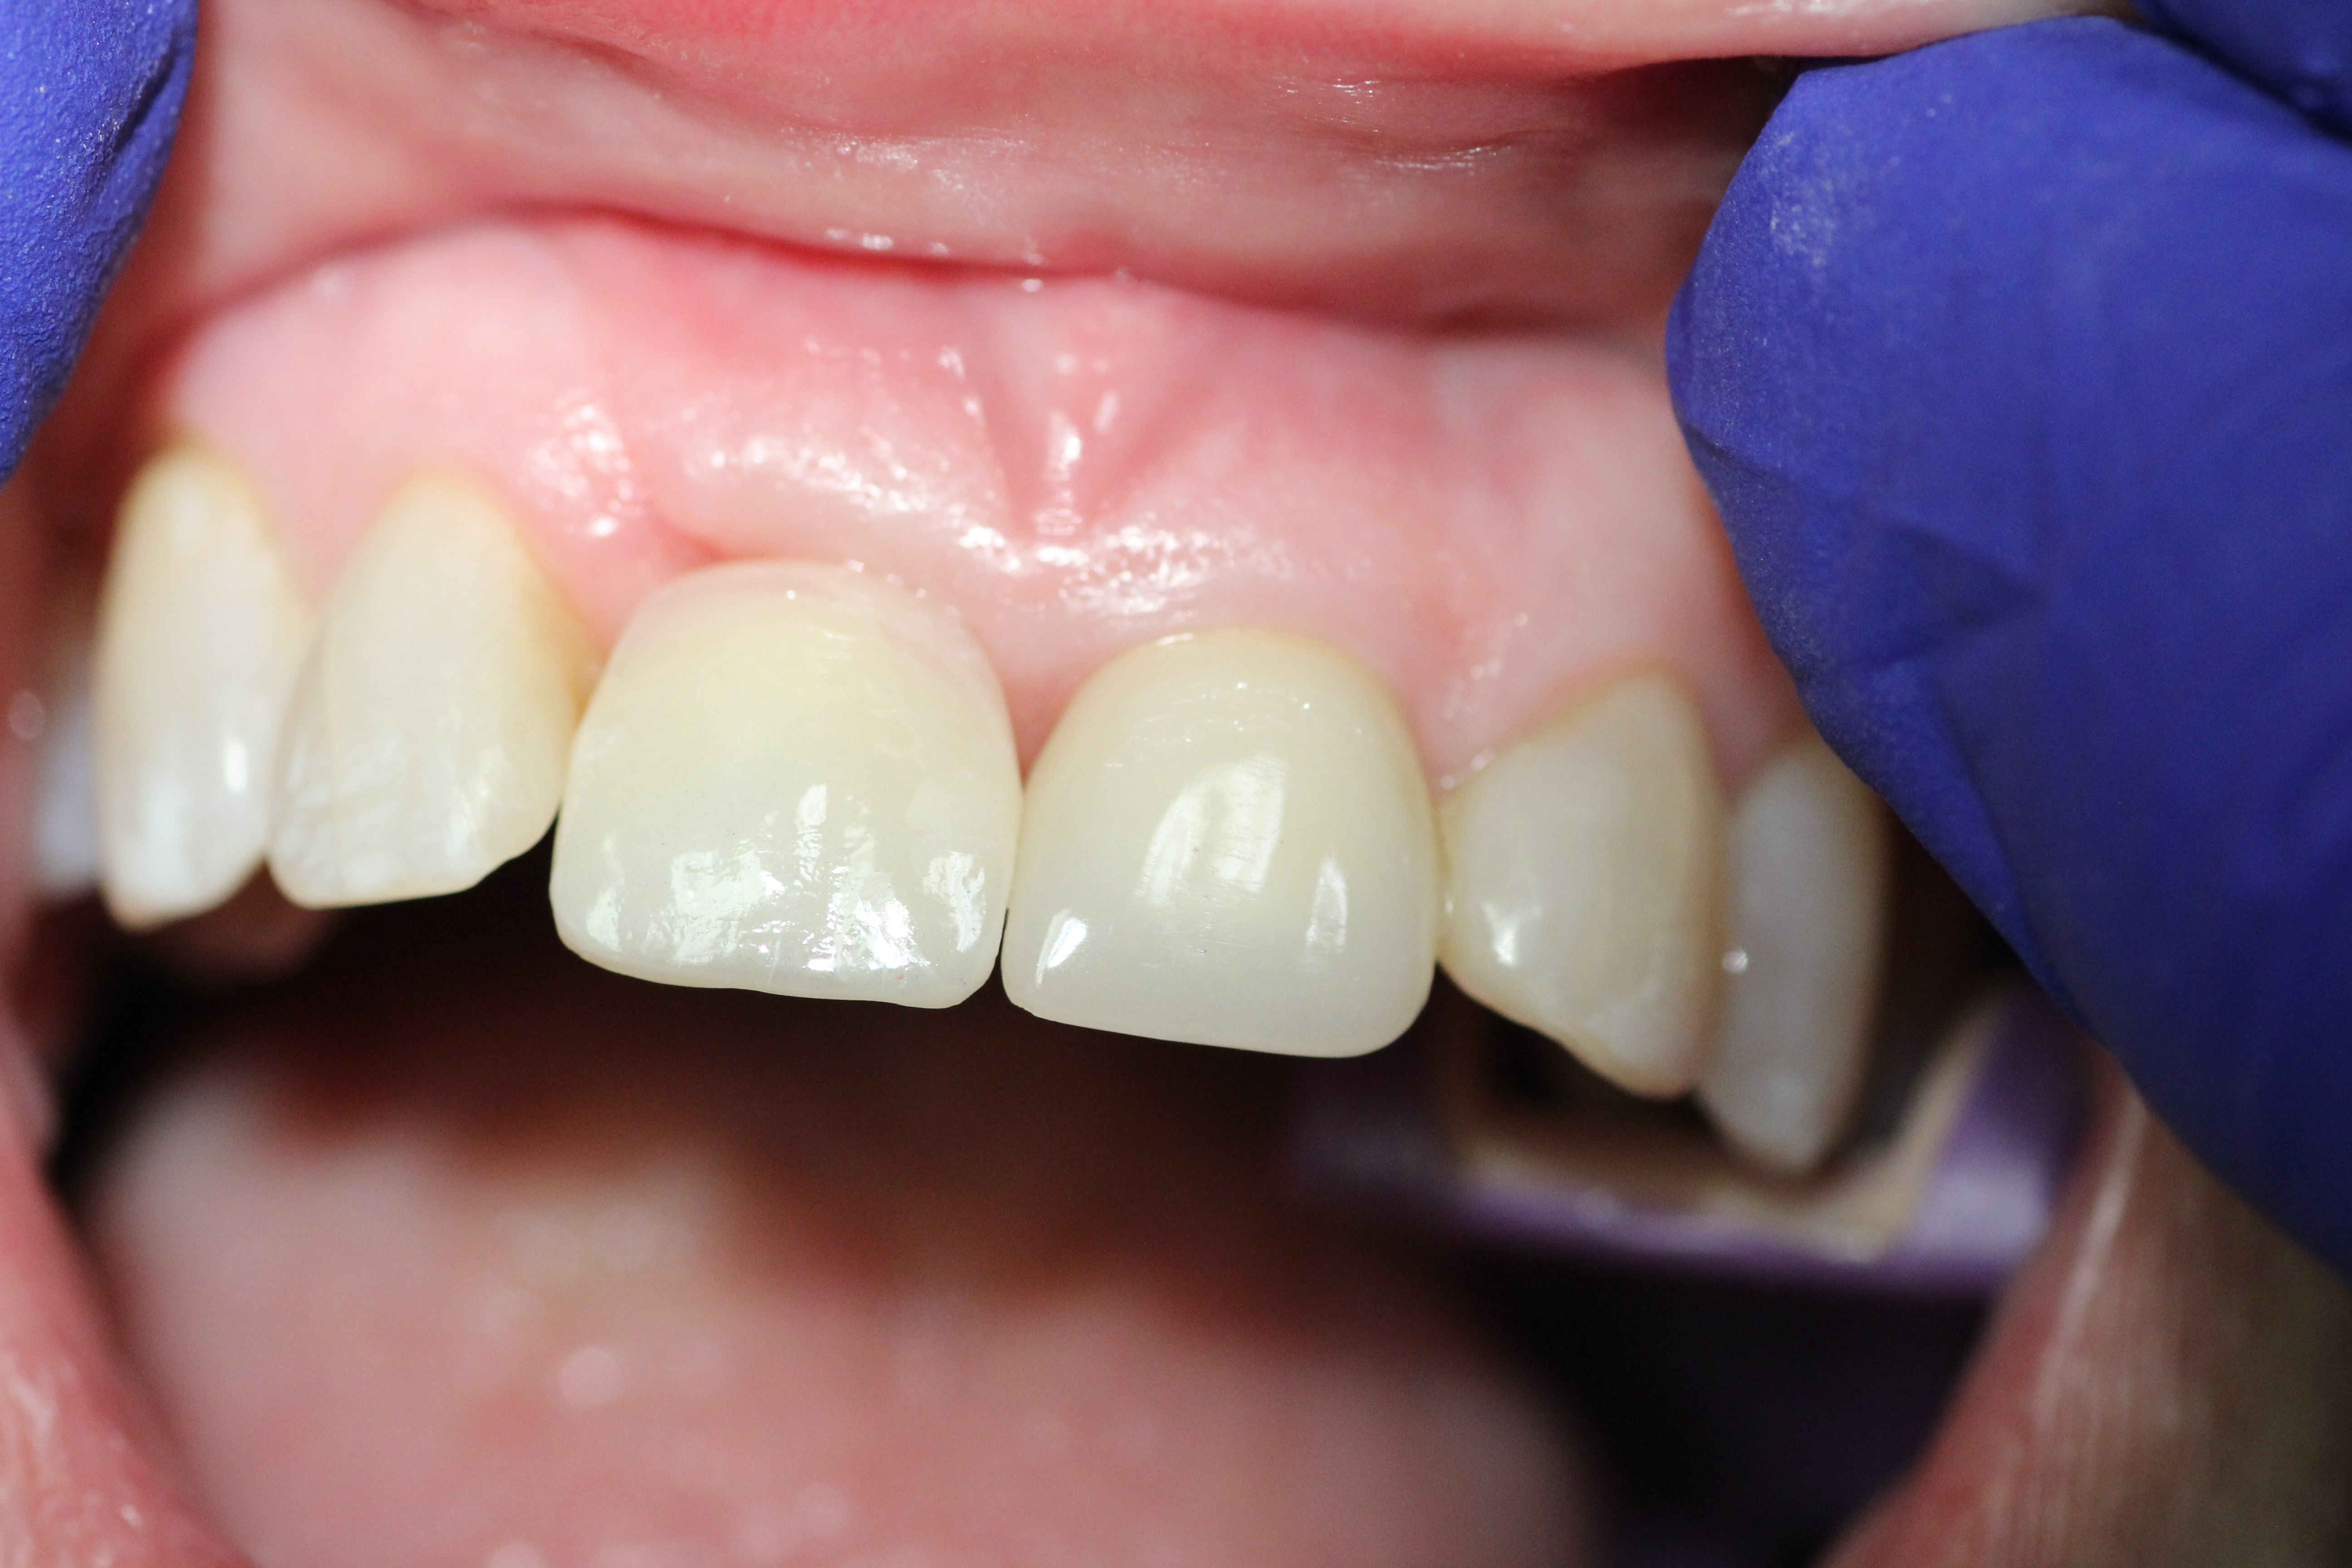

- Final Crown.